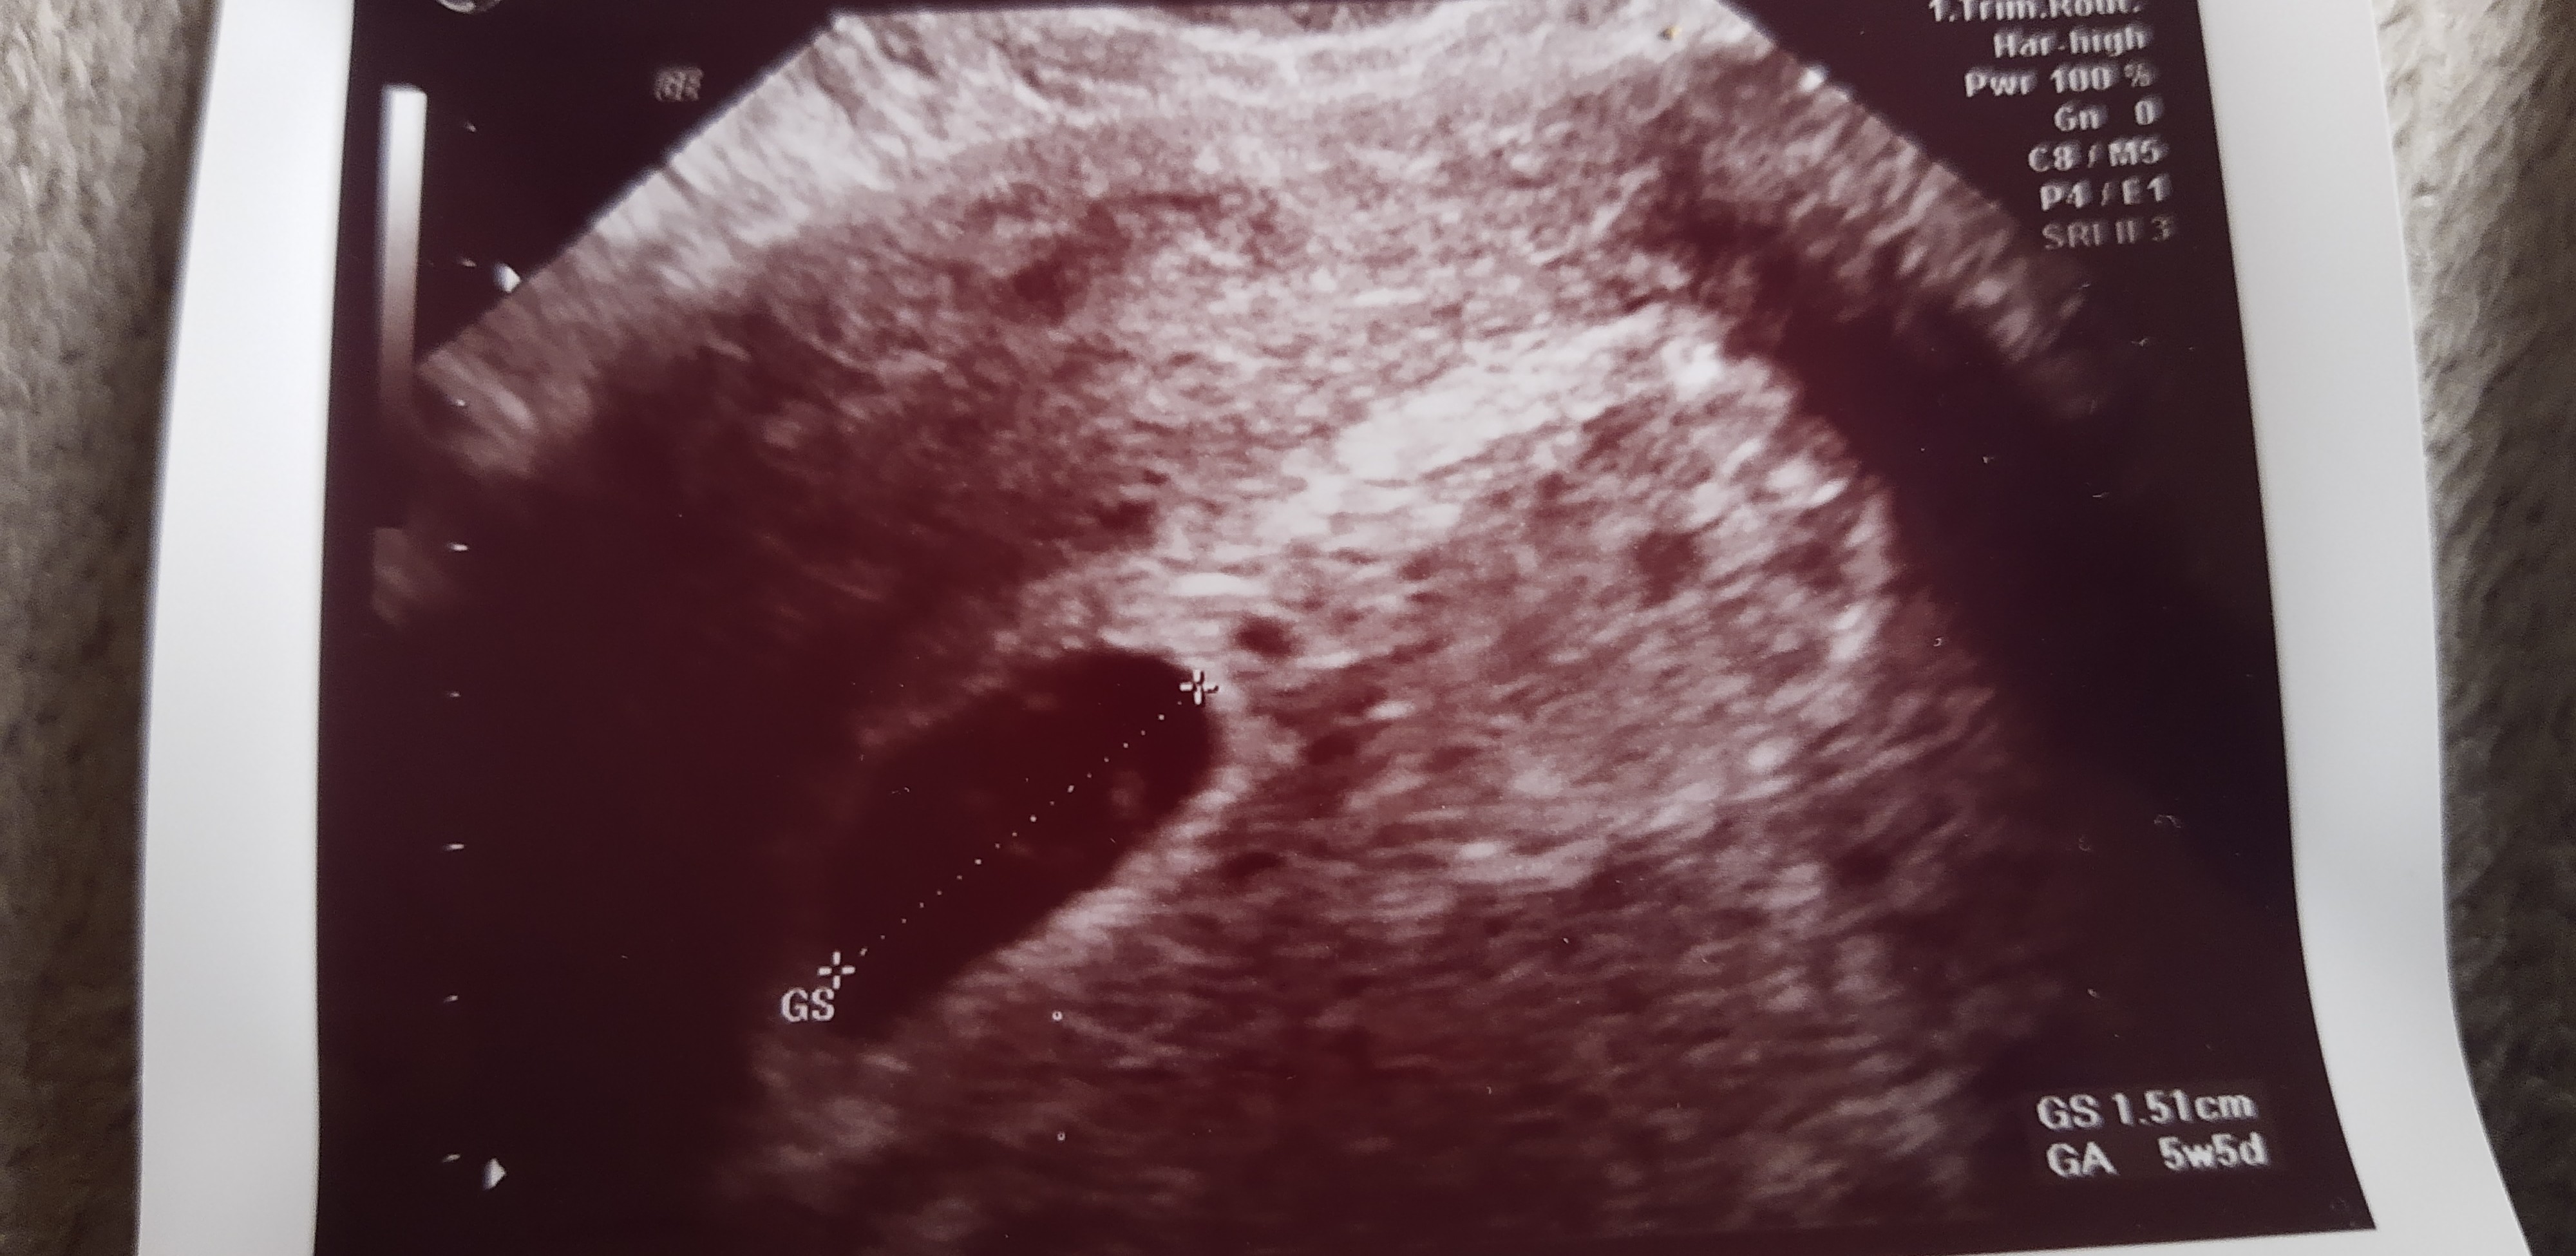

jeśli tydzień temu było 5+5 to teraz będzie 6÷5 więc możliwe że jest szansa.Kobietki potrzebuje porady pisałam ostatnio tutaj trafiłam alarmowo tydzień temu do ginekologa z śluzem brązowym wyszło że ciąża młodsza 10 dni ale moje @ bardzo nieregularne z USG wyszło 5 tc i 5 dni pęcherzyk ciążowy na miejscu i żółtkowy również. Teraz pytanie 25.01 mam umówioną wizytę u innego gin czy jest możliwość jak pójdę że będzie zarodek i serduszko?

Dodaje zdjęcie USG co myślicie ?Zobacz załącznik 1487961

Według mnie jest szansa na jedno i drugie, ale nie jest to wyznacznikKobietki potrzebuje porady pisałam ostatnio tutaj trafiłam alarmowo tydzień temu do ginekologa z śluzem brązowym wyszło że ciąża młodsza 10 dni ale moje @ bardzo nieregularne z USG wyszło 5 tc i 5 dni pęcherzyk ciążowy na miejscu i żółtkowy również. Teraz pytanie 25.01 mam umówioną wizytę u innego gin czy jest możliwość jak pójdę że będzie zarodek i serduszko?

Ja 5.01 miałam 5+2 i nie było nawet ciałka żółtego, tylko pęcherzyk. 13.01 był już zarodek z serduszkiemDziękuję kochane za odpowiedź. Śluz uspokoił się w miarę biorę duphaston 3x1 nie wiem kompletnie co robić jestem kłębkiem nerwów i tylko czytam w internecie![]()